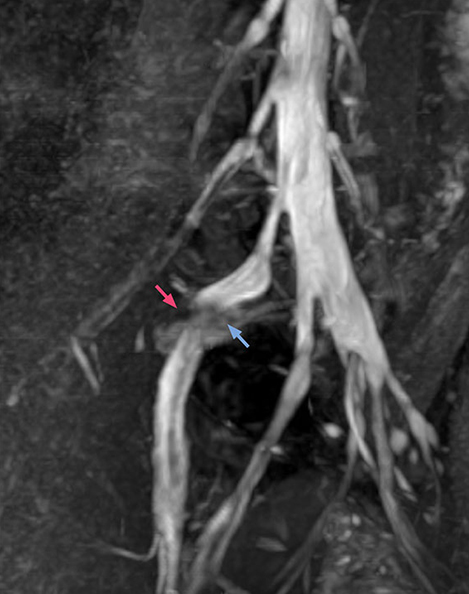

“In such case, we would then browse through axial T2-weighted MR images slice by slice and mentally reconstruct the actual situation based on both radiculography and MRI. Fortunately, NerveVIEW can now very well show nerve courses and presence of nerve compression or edema in one single image series.” “We have often seen NerveVIEW directly depict details of the nerve compression that were not observed by radiculography. Therefore, we think that with NerveVIEW we can reduce the number of invasive examinations, especially for some patients with lumbar plexus symptoms.”

“Before NerveVIEW, diagnosis by MRI alone was sometimes difficult, unless there was a strong suspicion based on clinical symptoms,” says Shoji Yabuki, MD, DMSc, Orthopedic surgeon at Fukushima Medical University School of Medicine. “This is why we routinely perform selective lumbosacral radiculography (nerve root block) and x-ray in such cases. However, radiculography can only depict nerves as far as the contrast agent reaches. When a nerve is distorted by compression, the contrast agent will not pass through this compressed area, preventing us from evaluating the full nerve compression.”

The key concept in MR neurography, Dr. Yabuki stresses, is the ability to directly visualize spinal nerves, versus inferring the presence of pathology indirectly. “Before NerveVIEW, we estimated compression of the nerve by looking for the presence or absence of fat signal on other MR images,” he says.

“For example, in sagittal images, when the presence of fat is observed in the intervertebral foramen, it suggests that there is a margin around the nerve. Similarly, the absence of fat indicates that the nerve is being compressed. So, we used to deduce nerve compression indirectly. With NerveVIEW, however, we can observe the condition of the nerves directly, regardless of the presence or absence of fat. We always prefer such direct observation of anatomy over having to make an inference about it.”

“Although symptoms of typical disc herniation and atypical hernia are very similar, the actual site of herniation is different. It is therefore important to characterize the nerve’s condition both inside and outside of the intervertebral foramina. “Conversely, if we see no abnormality in NerveVIEW, we can assume at least that there is no severe condition that requires surgery. Like this, it can help us avoid unnecessary surgery. NerveVIEW can have a tremendous impact in this way.”

“The intra-luminal signal of veins, especially around the intervertebral space, can be suppressed well with NerveVIEW. As a result, we can easily observe the detailed nerve structure around the posterior ganglion,” he says. “This is why we use 3D NerveVIEW for intraforaminal stenosis and extraforaminal stenosis/herniation (lateral disc herniation). On the other hand, if herniation is suspected to exist inside the dorsal root ganglion (DRG), balanced TFE or ProSet-FFE is applied. NerveVIEW is not suitable for evaluating the median type of herniation.” The SE-EPI DWI-based method for MR neurography works well for large FOV exams like whole-body MRI, but focal examination of nerves is often limited by the attainable spatial resolution (both inplane and slice direction) and geometric distortion. “3D NerveVIEW achieves higher in-plane resolution – close to our other routine spine sequences – and the source images can be used instead of adding a fat-suppressed T2-weighted sequence,” Tanji says.

“NerveVIEW can clearly show nerve courses and presence of nerve compression. However, when multiple abnormalities are seen, it can still be hard to determine which nerve is causing the symptoms,” says Dr. Yabuki. “In our experience so far, we see abnormal findings on NerveVIEW in about 70% of elderly patients. As the pain is usually caused by only one nerve, we thus need to find the exact corresponding nerve.” “With a nerve root block, the patient's pain is improved by infiltration of local anesthesia directly around the nerve root considered to be responsible. Knowing such nerve root block findings prior to image interpretation, helps to easily recognize abnormal findings on NerveVIEW as well. In other words, without a priori knowledge, based on symptoms and/or nerve root block findings, we must be aware of the possibility of overdiagnosis.”